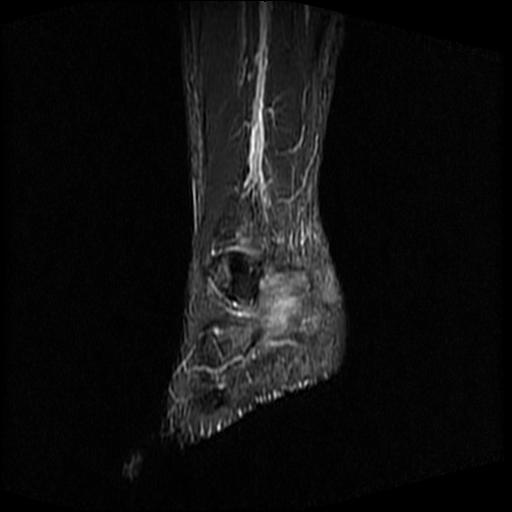

标题: MRI0968:女性,70岁,跟骨信号异常 [打印本页]

标题: MRI0968:女性,70岁,跟骨信号异常

女性,70岁,右侧跟骨疼痛2个月,负重时加剧,不负重时不疼。

胫骨下段,跟骨、距骨可见斑片状异常信号区;考虑:转移瘤

跟骨长t1长t2信号异常,边缘模糊(肿瘤一般边界清楚,故肿瘤不考虑),压脂像呈高信号--骨髓水肿(炎症?)。